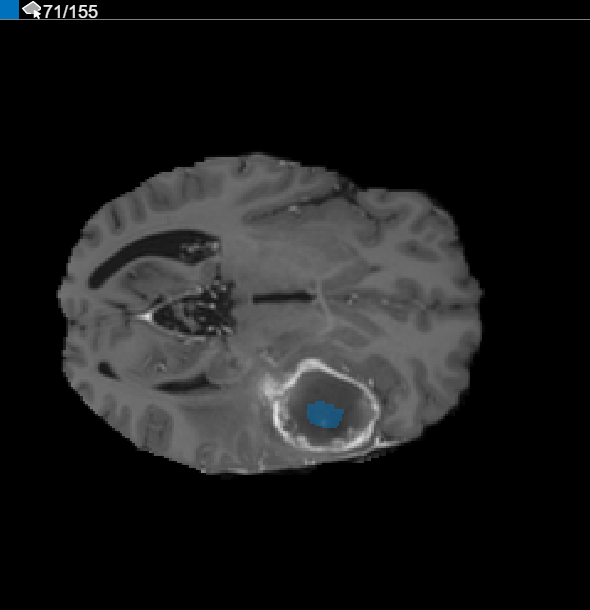

Refine the Interpolated ROIs

After using interpolation, check the individual slices to see if the interpolation created satisfactory ROIs. Note that the ROI on slice 71 does not fill the entire object that you want to segment. You can manually adjust the ROI using the Paint Brush tool. Alternatively, you can use one of the tools on Automate tab. For example, you can use Active Contours to grow the ROIs on the slices where it does not fill the full size of the tumor. You can also use the Add Algorithm to specify your own algorithm to operate on the ROIs.